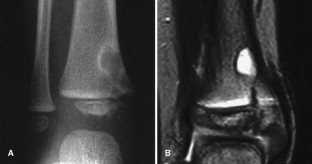

Fig. 1.